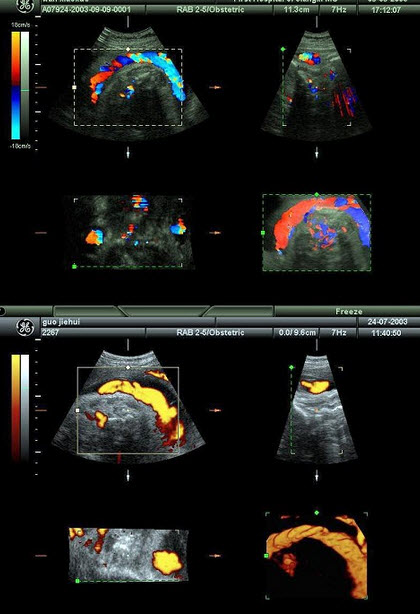

14、单项选择题 女性腹腔最低部位是()